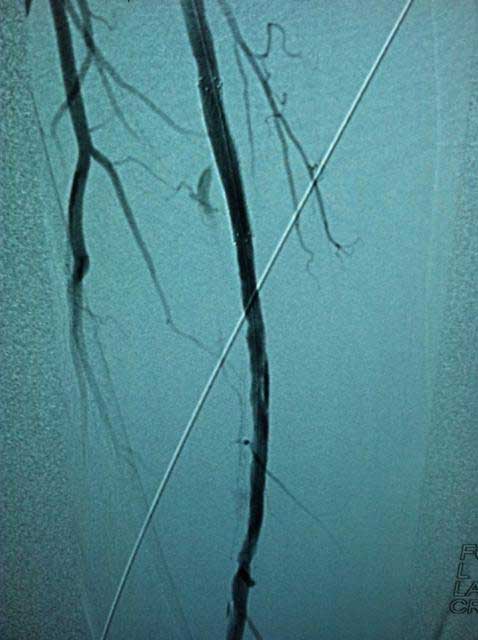

Interventional case 1